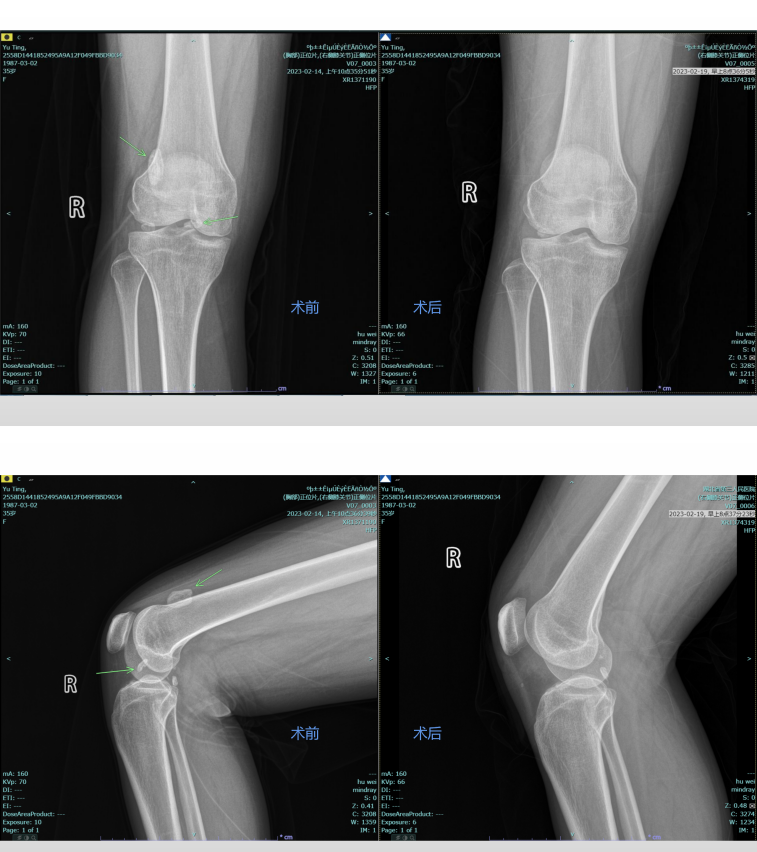

术前及术后对比

术后第二天,余女士被告知可以下地活动,“做了手术不是应该在床上躺着吗?这么快就下地真的没问题吗?”余女士满脸疑惑。“放心吧,现在不同以往了,微创手术旨在尽量小的创口下解决患者的问题,创口小了,术后恢复自然就快,所以就能早期下床活动”。王显勋解释到,“你再试试弯一下膝盖,看看还有没有卡住的感觉”。在管床医生的帮助下,余女士缓缓屈伸膝关节,发现之前困扰自己的症状已经不复存在了,在之后的膝关节锻炼中,也没有再出现“卡住”的感觉,这终于让余女士放下了心。最终,在医护的悉心照料下,术后第五天,余女士恢复良好,顺利出院。